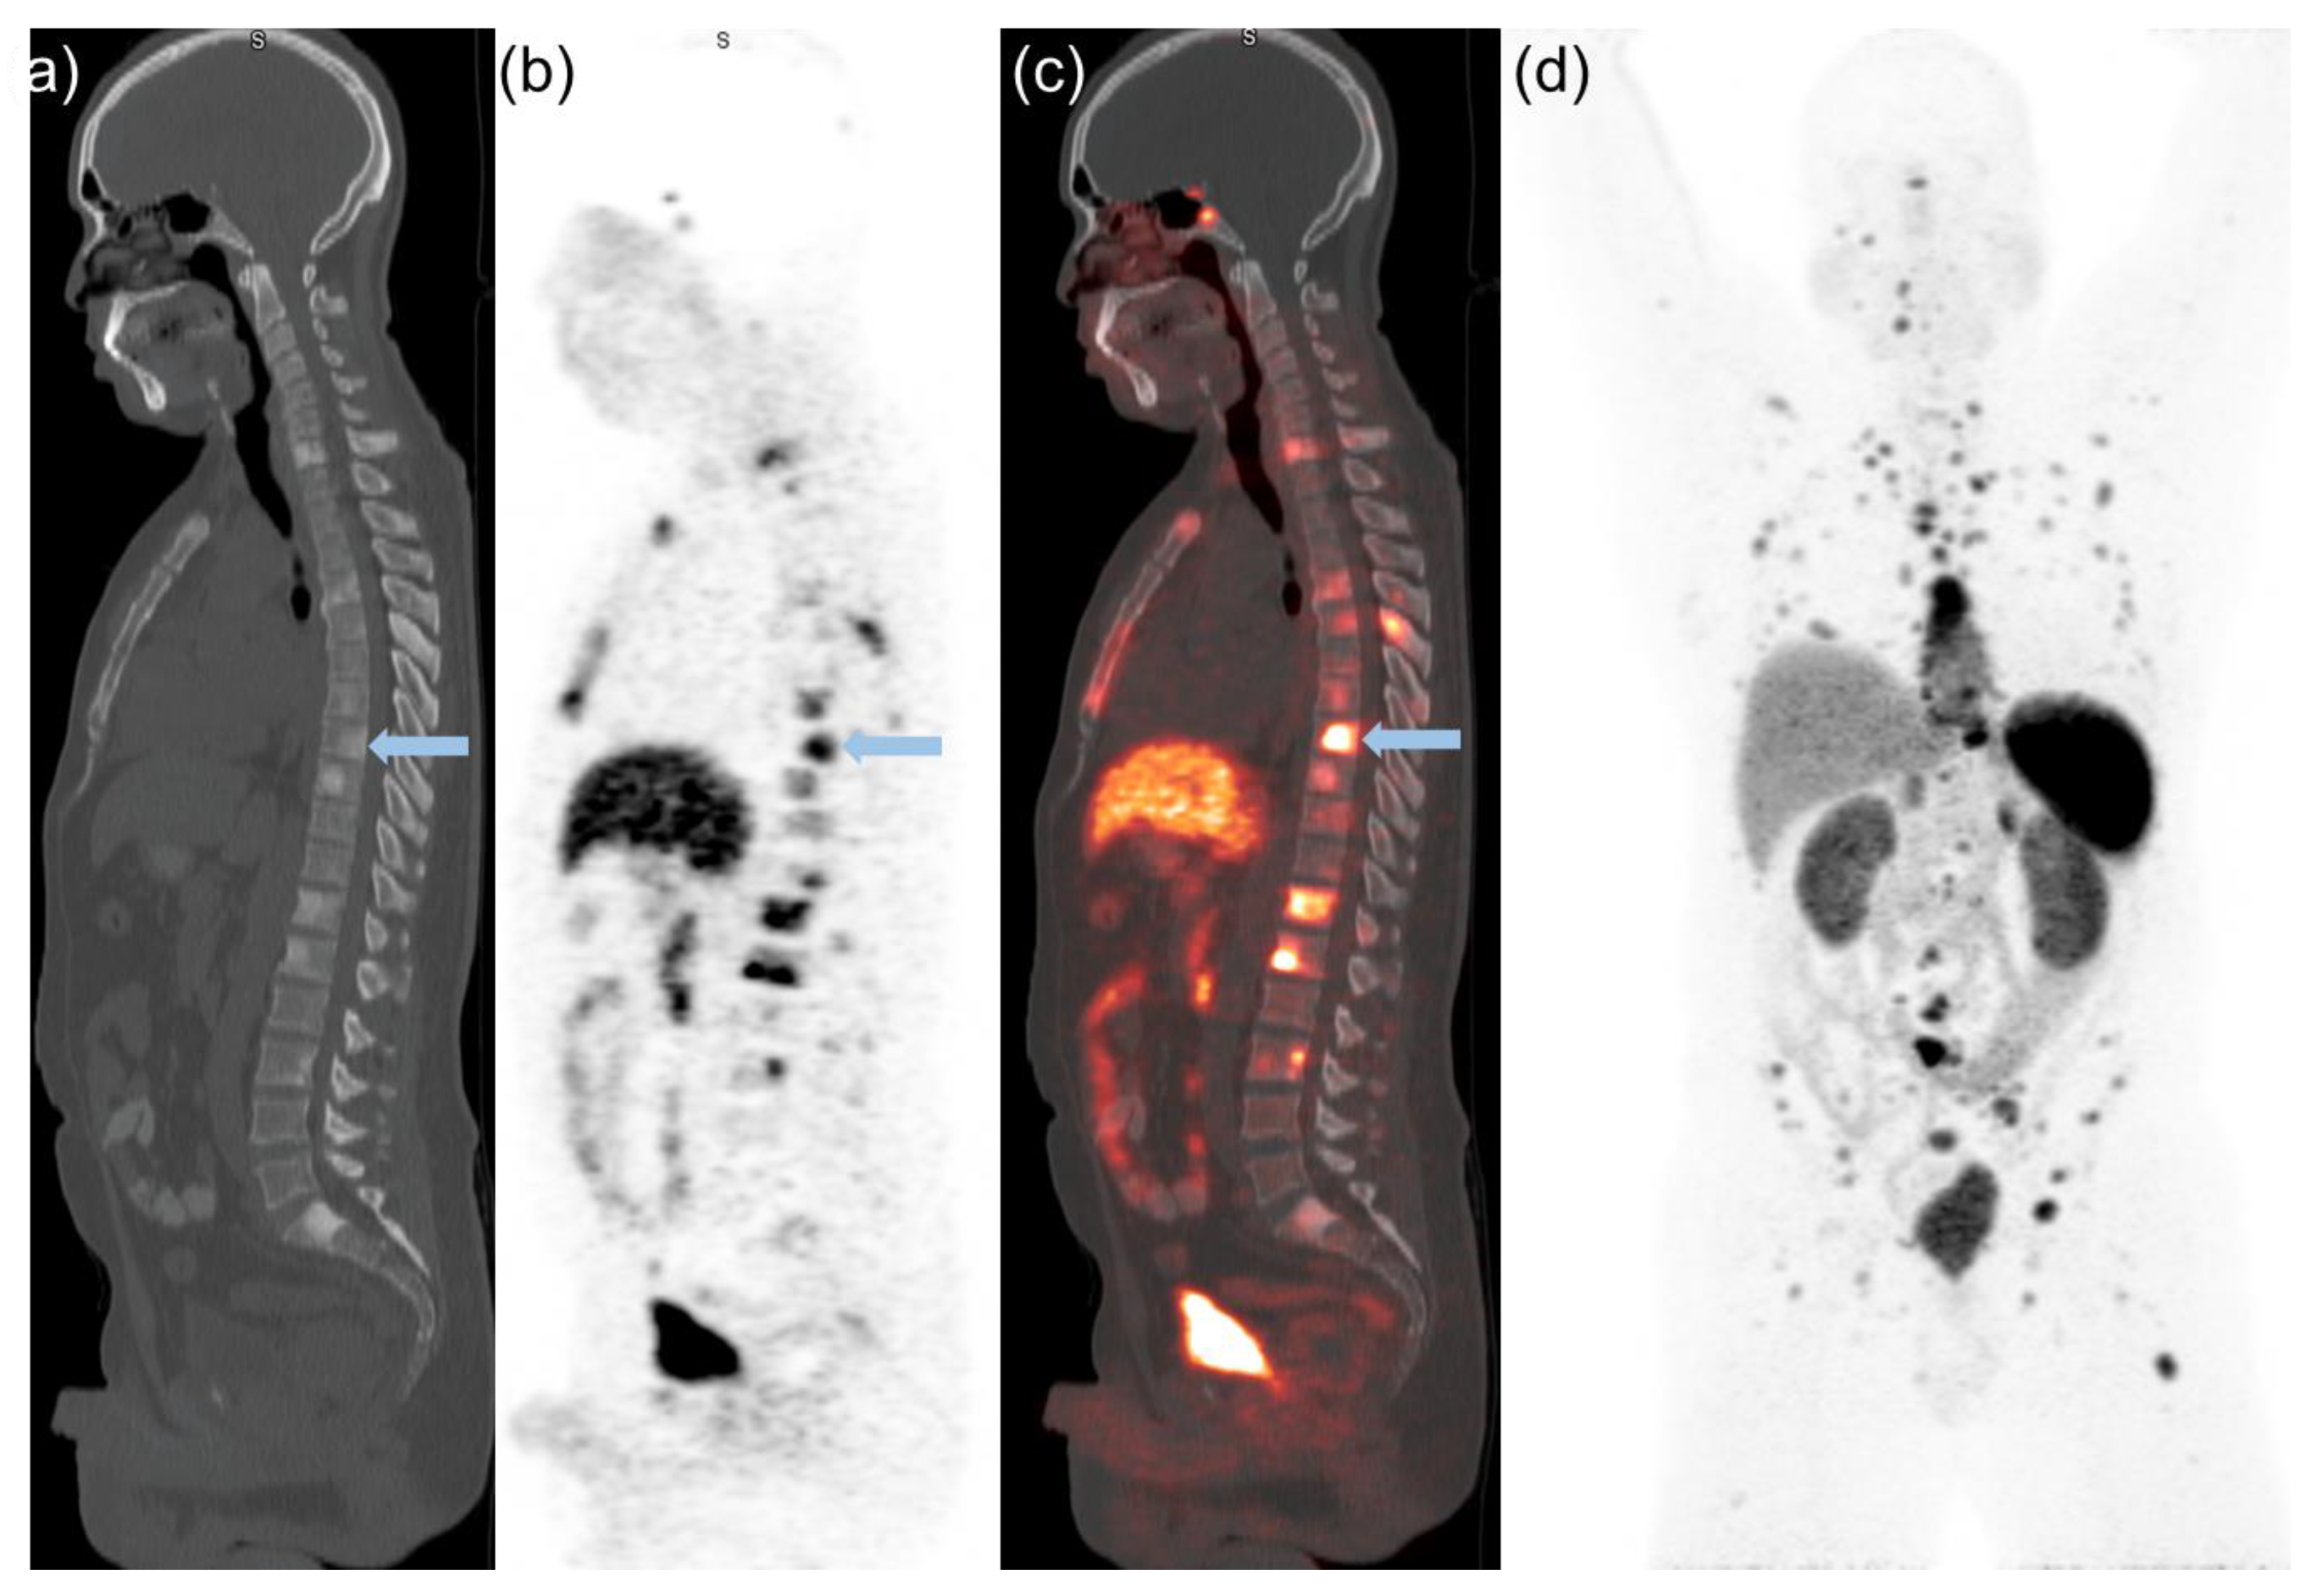

Semiquantitative PET and Visual Analysis